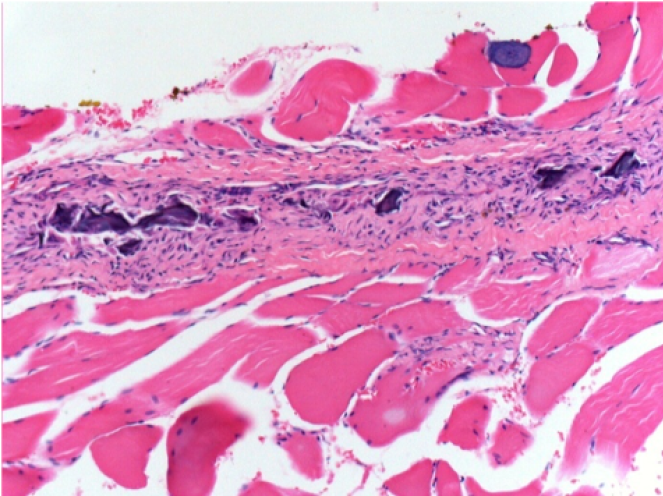

1 mes después de la inyección de Endopeel

1 mes después de la inyección de Endopeel 0,1 ml en el músculo pretibial derecho.

¡Lo que se ve en negro en las imágenes no es una necrosis como podrían imaginar algunos científicos!

De hecho, hay que tener en cuenta 4 conclusiones

- un artefacto de coloración

- una ausencia de necrosis

- una apoptosis

- un proceso biorregenerativo

L : Control-100xD30

R:100xD30

R :400xD30

08